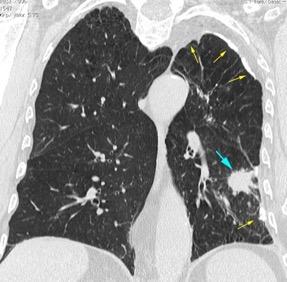

< 80% hallazgos pulmonares. Colección con calcificaciones. Micronódulos en intersticio subpleural y broncovascular con engrosamiento septal. Respuesta paradójica frecuente.

Vorsted MJ et al. Tuberculous pleural effusions: advances and controversias. J Thorac Dis 2015/ Wen P et al. Risk factors for tuberculous empyema in pleural tuberculosis patients. Sci Rep. 2019.